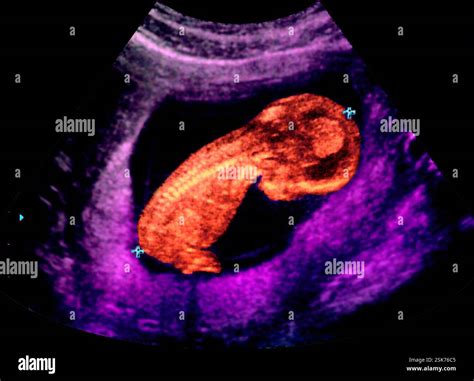

A Thirteen Week Ultrasound is a routine prenatal examination typically performed between 12 and 13 weeks of pregnancy. This ultrasound is crucial for several reasons, including assessing the baby's growth, checking for any potential abnormalities, and determining the due date more accurately. It is often combined with a nuchal translucency scan, which measures the fluid at the back of the baby's neck to screen for chromosomal abnormalities.

During the Thirteen Week Ultrasound, you will lie on an examination table with your abdomen exposed. A gel will be applied to your belly, and a transducer will be moved across the area to capture images of the baby. The procedure is painless and typically takes about 20-30 minutes.

The ultrasound technician will look for several key indicators, including:

• Baby's Heartbeat: The heartbeat should be clearly visible and audible.

• Baby's Measurements: The baby's crown-to-rump length (CRL) will be measured to assess growth and development.

• Placenta Location: The position of the placenta will be checked to ensure it is not covering the cervix (placenta previa).

• Amniotic Fluid Levels: The amount of amniotic fluid will be evaluated to ensure it is within normal ranges.